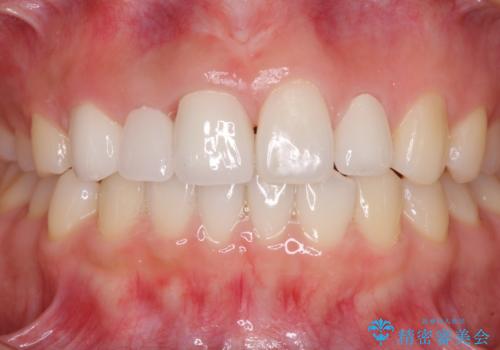

お仕事で多忙な患者様であったため、治療期間は予定の2倍くらいの期間がかかってしまいました。そのため、治療期間中に仮歯が外れてしまったり、痛みが出てしまったりとご迷惑をかけてしまうことがありました。

すべてのクラウンが装着された後は、痛みやかみ合わせの不具合が解消されたことはもちろん、審美的にも大きく改善され、患者様には大変満足していただけました。